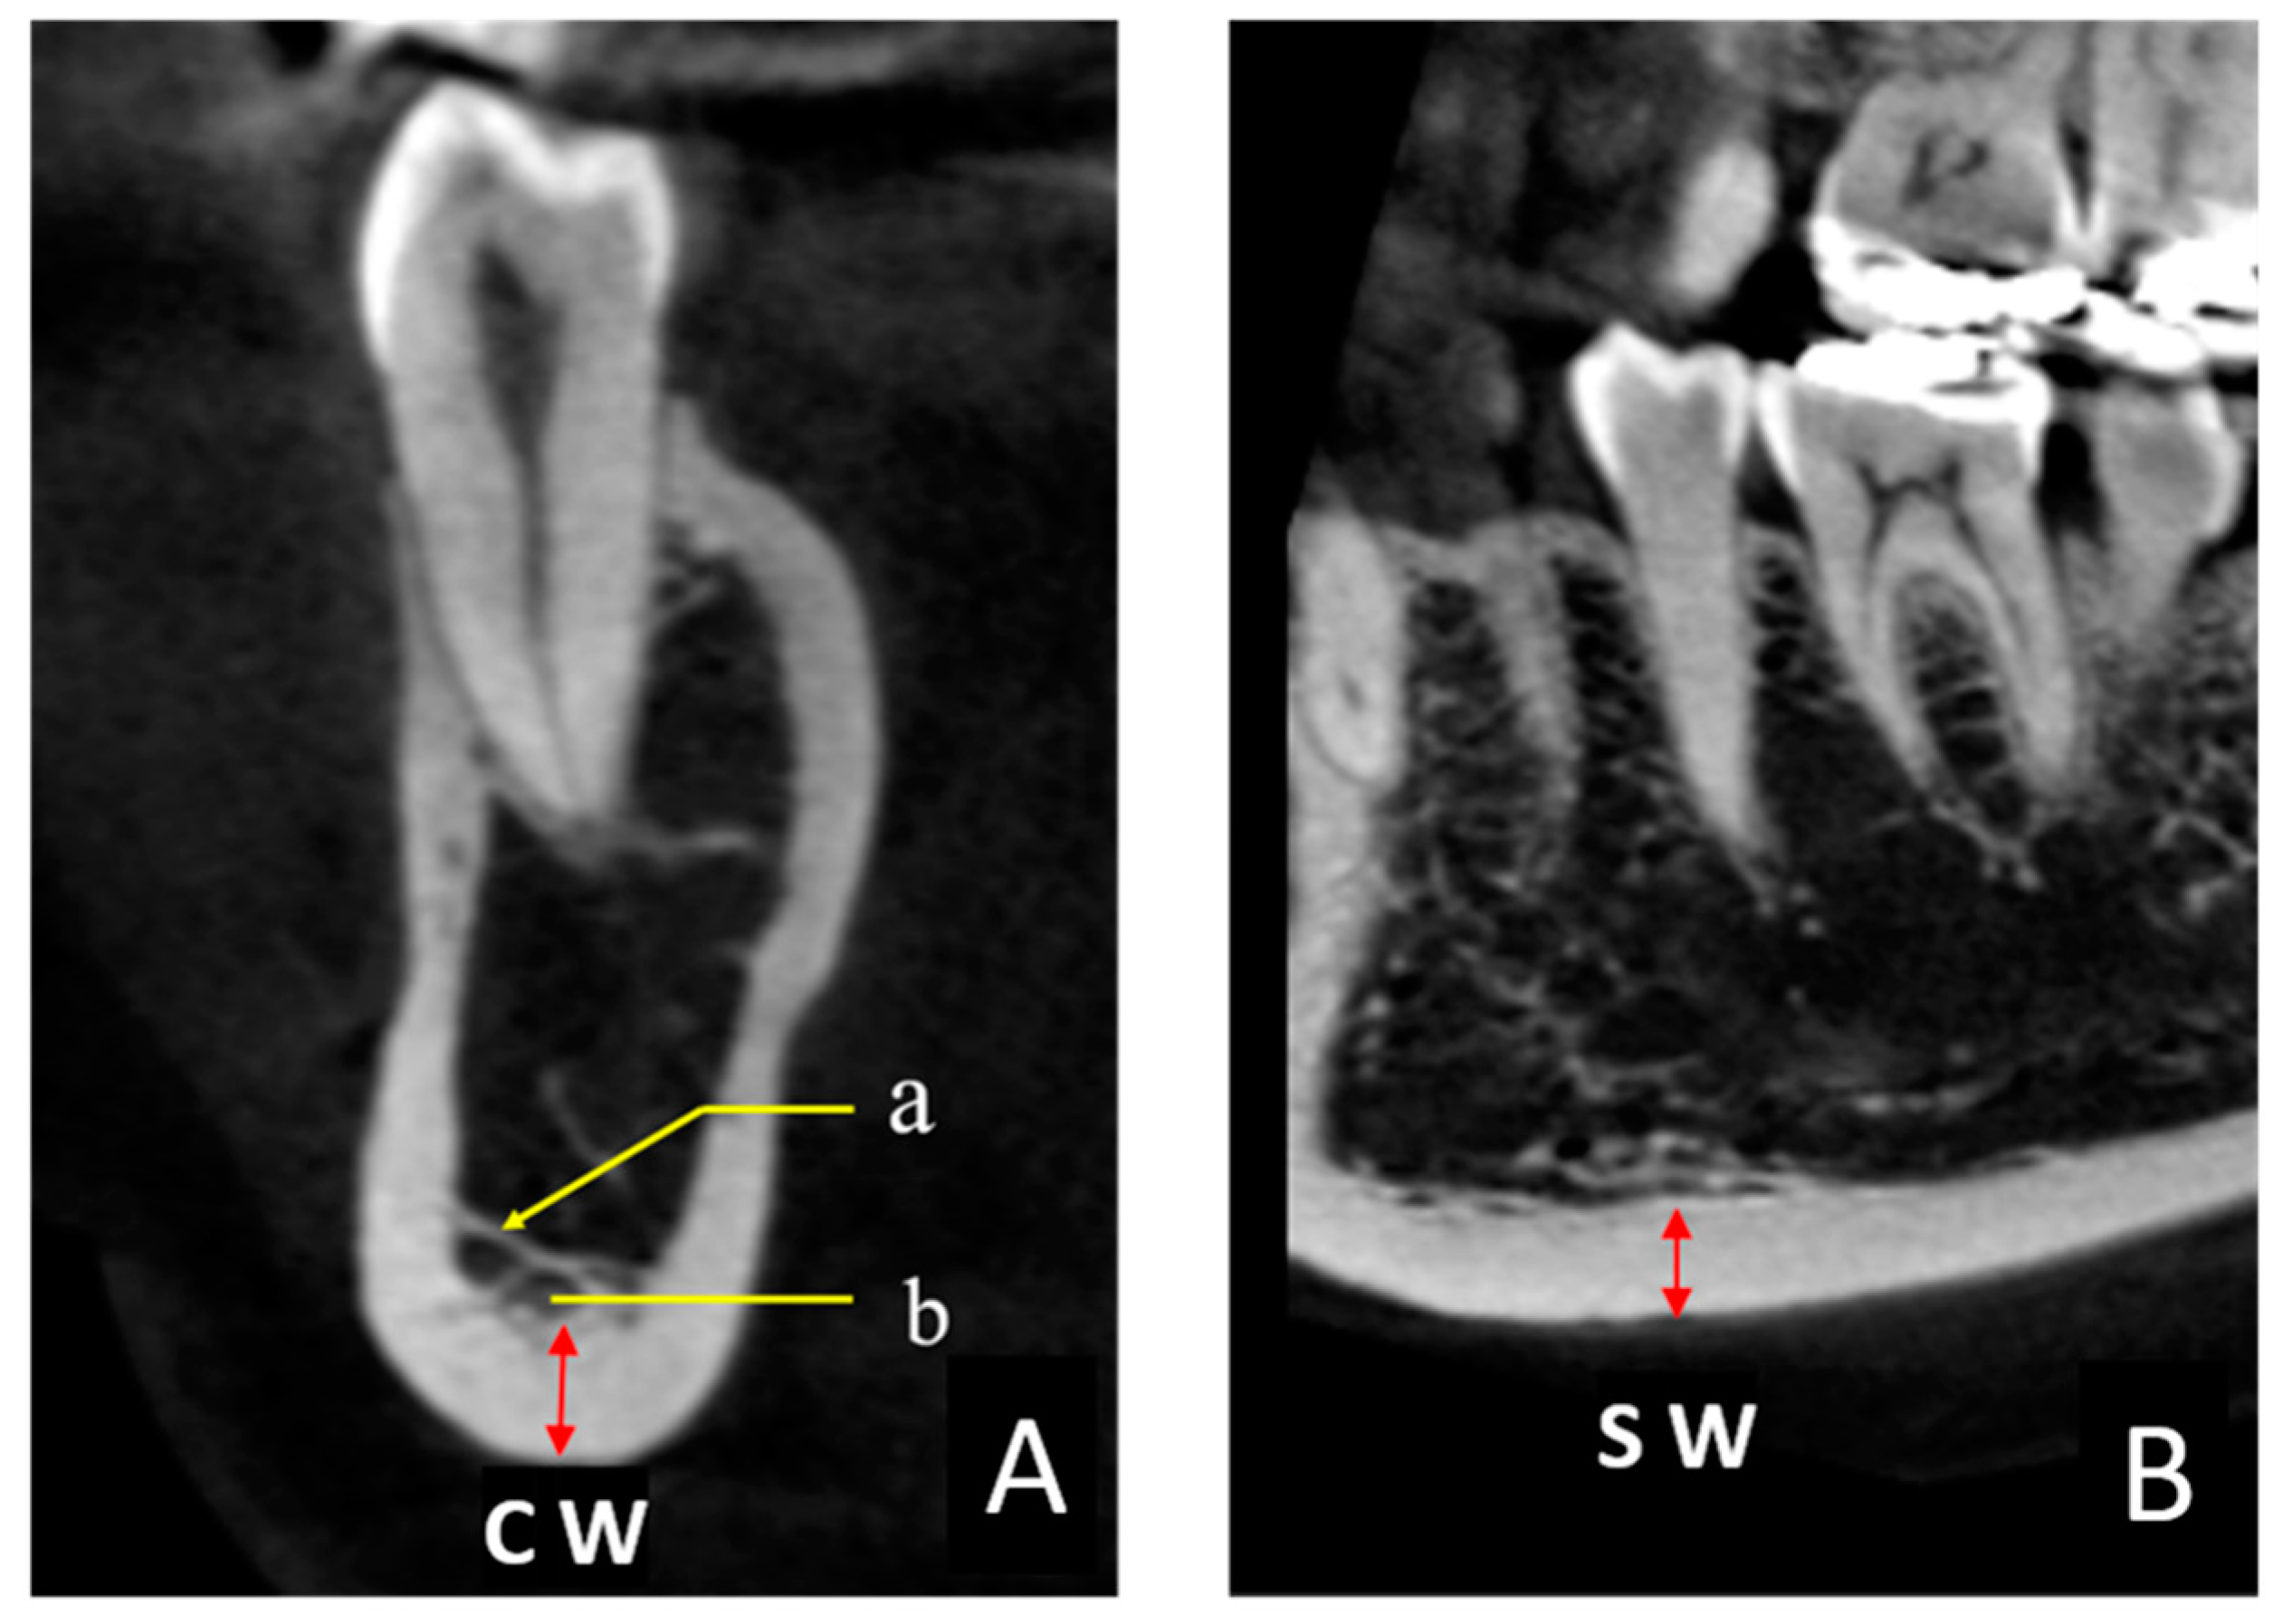

The thickness of the mandibular inferior cortical bone was measured in all CBCT images. These measurements were performed in two cross sections to obtain the coronal width (CW) and sagittal width (SW) twice on each side in 0.1-mm increments by one examiner (K.S.) using the image analysis software described above (Figure 2A, B). The target area was immediately below the mental foramen, and the Hounsfield unit (HU) display tool provided with the software was used as an indicator to digitally measure the bone tissues with a value of ≥1000 [19]. The HU value could be easily displayed on the viewer image by manipulating the pointer in any region. Finally, the CW and SW values were averaged to obtain the mandibular cortical width (MCW). When the CBCT imaging site was the whole jaw, two sites were measured (one on the left and one on the right), and when the imaging site was only one side, one site was measured. In some cases, the bone margin immediately below the mental foramen was not included in the imaging area, in which case an adjacent area, such as that immediately below the first molar, was measured.

Figure 2. (A) CBCT coronal section of a C2 (Figure 1, B) case. (a) Trabecular structures running buccolingually. (b) Areas with small virtual HU values (578) were not included in the measurement, and areas with HU values of >1000 (red arrows) were measured to obtain the coronal width (CW). (B) Sagittal section of the same region. The sagittal width (SW) was measured along with the CW, and the mean value of the CW and SW was defined as the mandibular cortical width.